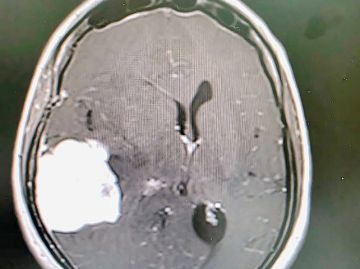

وأوضح تجمع المدينة المنورة الصحي أن نتائج الفحوصات الطبية، وأشعة الرنين المغناطيسي، والأشعة المقطعية، أظهرت وجود ورم في الجزء الأيمن من الدماغ، مصحوبًا بارتشاح في الخلايا الدماغية المحيطة، ومؤشرات على وجود ضغط شديد على المناطق المجاورة في المخ.

وقد قرر الفريق الطبي التدخل الجراحي العاجل، حيث أُجريت عملية ميكروسكوبية دقيقة لاستئصال الورم بالكامل، وقد تكللت بالنجاح، ولله الحمد.